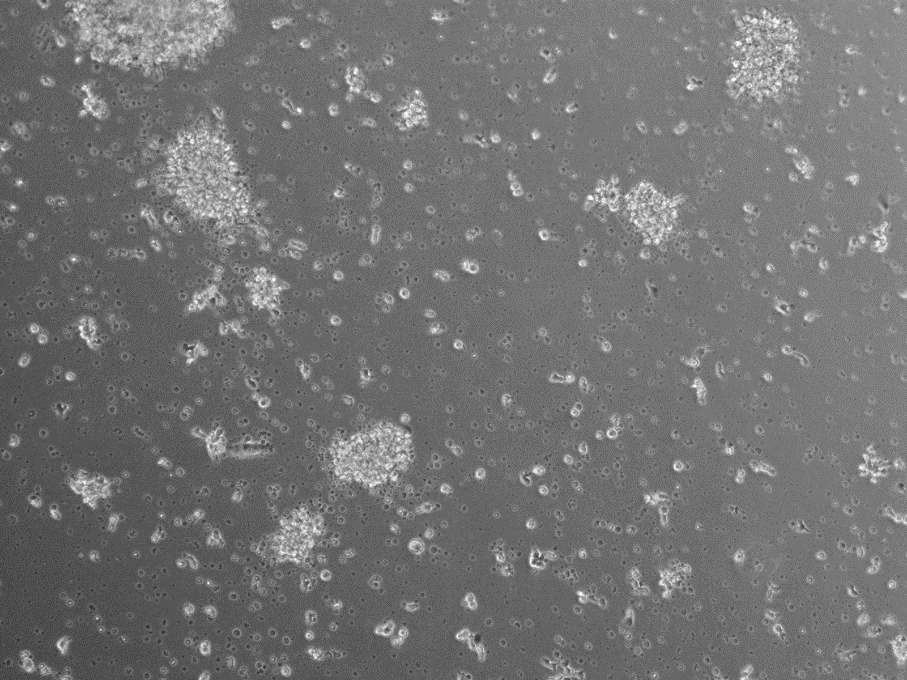

This program is primarily intended for students interested in the applications of biomaterials in cancer immunotherapy and infectious disease treatment. Students will learn how to prepare nanoparticles, investigate their interactions with immune cells, and analyze how these interactions modulate immune responses. In addition, they will gain hands-on experience in experimental design, data analysis, and the development of nanomedicine-based therapeutic strategies.